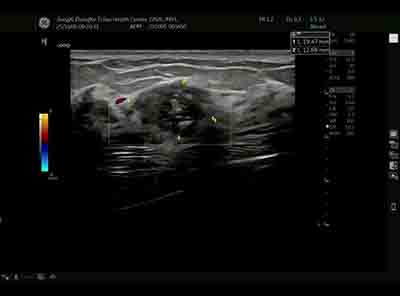

血流模式的精細(xì)評(píng)估 乳腺良惡性腫瘤的血流特征存在顯著差異。E11采用的超微細(xì)血流成像技術(shù)具有突破性意義:

準(zhǔn)確區(qū)分腫瘤邊緣與內(nèi)部血流分布 惡性腫塊通常表現(xiàn)為血流豐富、走行紊亂、動(dòng)靜脈瘺形成,而良性病變血流相對(duì)稀疏、走行規(guī)則。這種差異為鑒別診斷提供了重要參考。